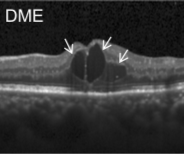

Eye diseases or ocular dysfunctions are fairly frequent in the general population, particularly among the elderly. The most significant anomalies in the eyes are choroidal neovascularization (CNV), diabetic macular edema (DME), and drusen accumulation in the macular region. In the recent decade, optical coherence tomography (OCT) has become one of the most rapidly evolving medical imaging technologies which can capture blood flow, polarization state, structural data, elastic properties, and molecular content, among other things, in biological tissues [1]. Optical diffraction and absorbance of biological tissues can be accurately measured with OCT and thus some diagnostic measures benefit from it.

Optical coherence tomography (OCT) images were selected from retrospective cohorts of adult patients from different hospitals around the world. OCT Images are labeled as (disease)-(randomized patient ID)-(image number by this patient) [11] and Fig 1 shows some examples of OCT images. Image properties are presented in Table II and the distribution of image quantity is presented in Table III. Custom image generators resize images to 224x224x3 and normalize them